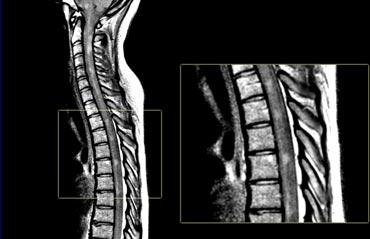

Tổn thương tủy sống

Các tổn thương tủy sống điển hình trong MS thường có kích thước tương đối nhỏ và nằm ở vị trí ngoại vi.

Chúng thường gặp nhất ở đoạn tủy cổ và thường có chiều dài dưới 2 đốt sống.

Tổn thương tủy sống kết hợp với tổn thương ở tiểu não hoặc thân não rất gợi ý chẩn đoán MS.

Tổn thương tủy sống ít gặp trong hầu hết các bệnh lý thần kinh trung ương khác, ngoại trừ ADEM, sarcoidosis và NMOSD.

Các hình ảnh cho thấy nhiều tổn thương đoạn ngắn trong tủy sống.

Trên chuỗi xung mật độ proton (PDW), tủy sống có tín hiệu thấp đồng nhất (tương tự dịch não tủy – CSF), tạo ra độ tương phản tốt giữa các tổn thương MS với dịch não tủy xung quanh và mô tủy bình thường.

Sử dụng ma trận 512 và kỹ thuật đồng bộ tim (cardiac gating) để đạt kết quả tối ưu.

Chuỗi xung STIR là một lựa chọn thay thế tốt cho PDW.

Cần đảm bảo có hai chuỗi xung khác nhau hoặc hai mặt phẳng chụp khác nhau.

Bệnh nhân NMOSD cho thấy tổn thương tủy sống lan rộng theo chiều dọc với phù nề rõ rệt. Viêm thần kinh thị giác hai bên. Chẩn đoán được xác nhận bằng hiệu giá kháng thể AQP4 là 1:1024.

Viêm tủy thị thần kinh

Một chẩn đoán phân biệt rất quan trọng cần lưu ý, đặc biệt ở bệnh nhân có viêm thần kinh thị giác hai bên và viêm tủy, là Rối loạn phổ viêm tủy thị thần kinh (NMOSD), trước đây gọi là bệnh Devic.

Đây là bệnh mất myelin do kháng thể kháng aquaporin hoặc MOG, trong đó các dây thần kinh thị giác và tủy sống thường bị tổn thương.

Nghĩ đến NMOSD khi có viêm tủy lan rộng theo chiều dọc (LETM được định nghĩa là trên 3 đốt sống) với giảm tín hiệu T1W và phù nề tủy sống.

Trên ảnh cắt ngang, các tổn thương thường liên quan đến chất xám trung tâm của tủy sống.

Điều này khác với MS, trong đó các tổn thương thường nhỏ hơn và nằm ở ngoại vi.